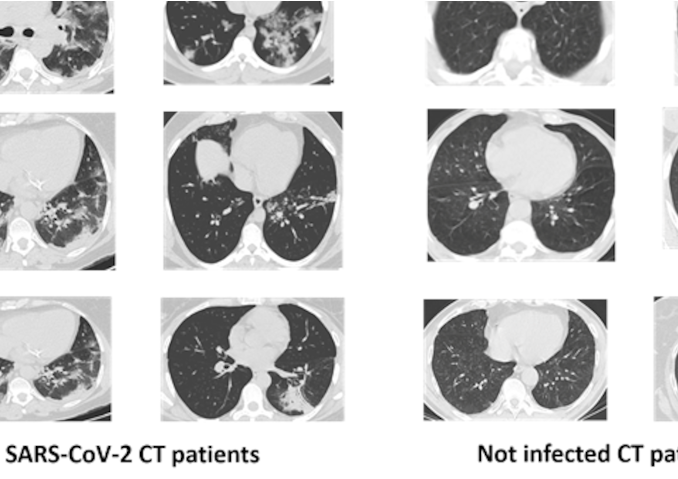

xDNN for SARS-CoV-2 identification in patient CT scans

This article is based on the work of Nitin Mane and his GitHub release: HIAS COVID-19 xDNN Classifier.